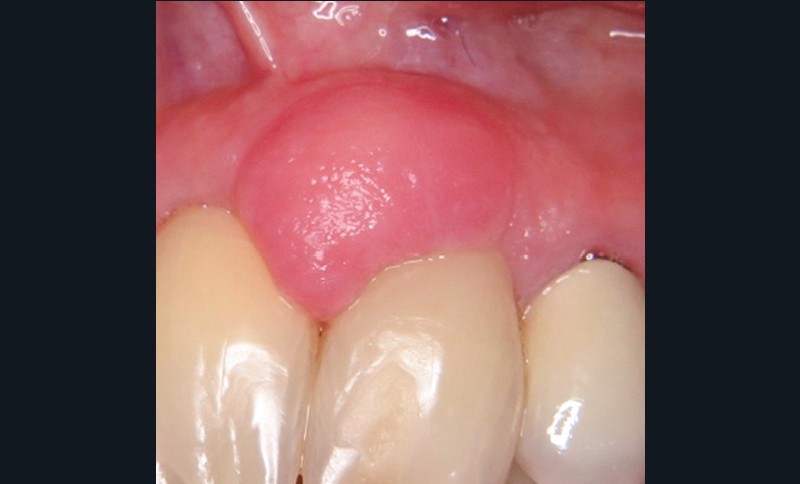

1. Épulis inflammatoire (plasmocytaire)

- Nodule indolore, pédiculé, érythémateux, parfois ulcéré (fig. 1a).